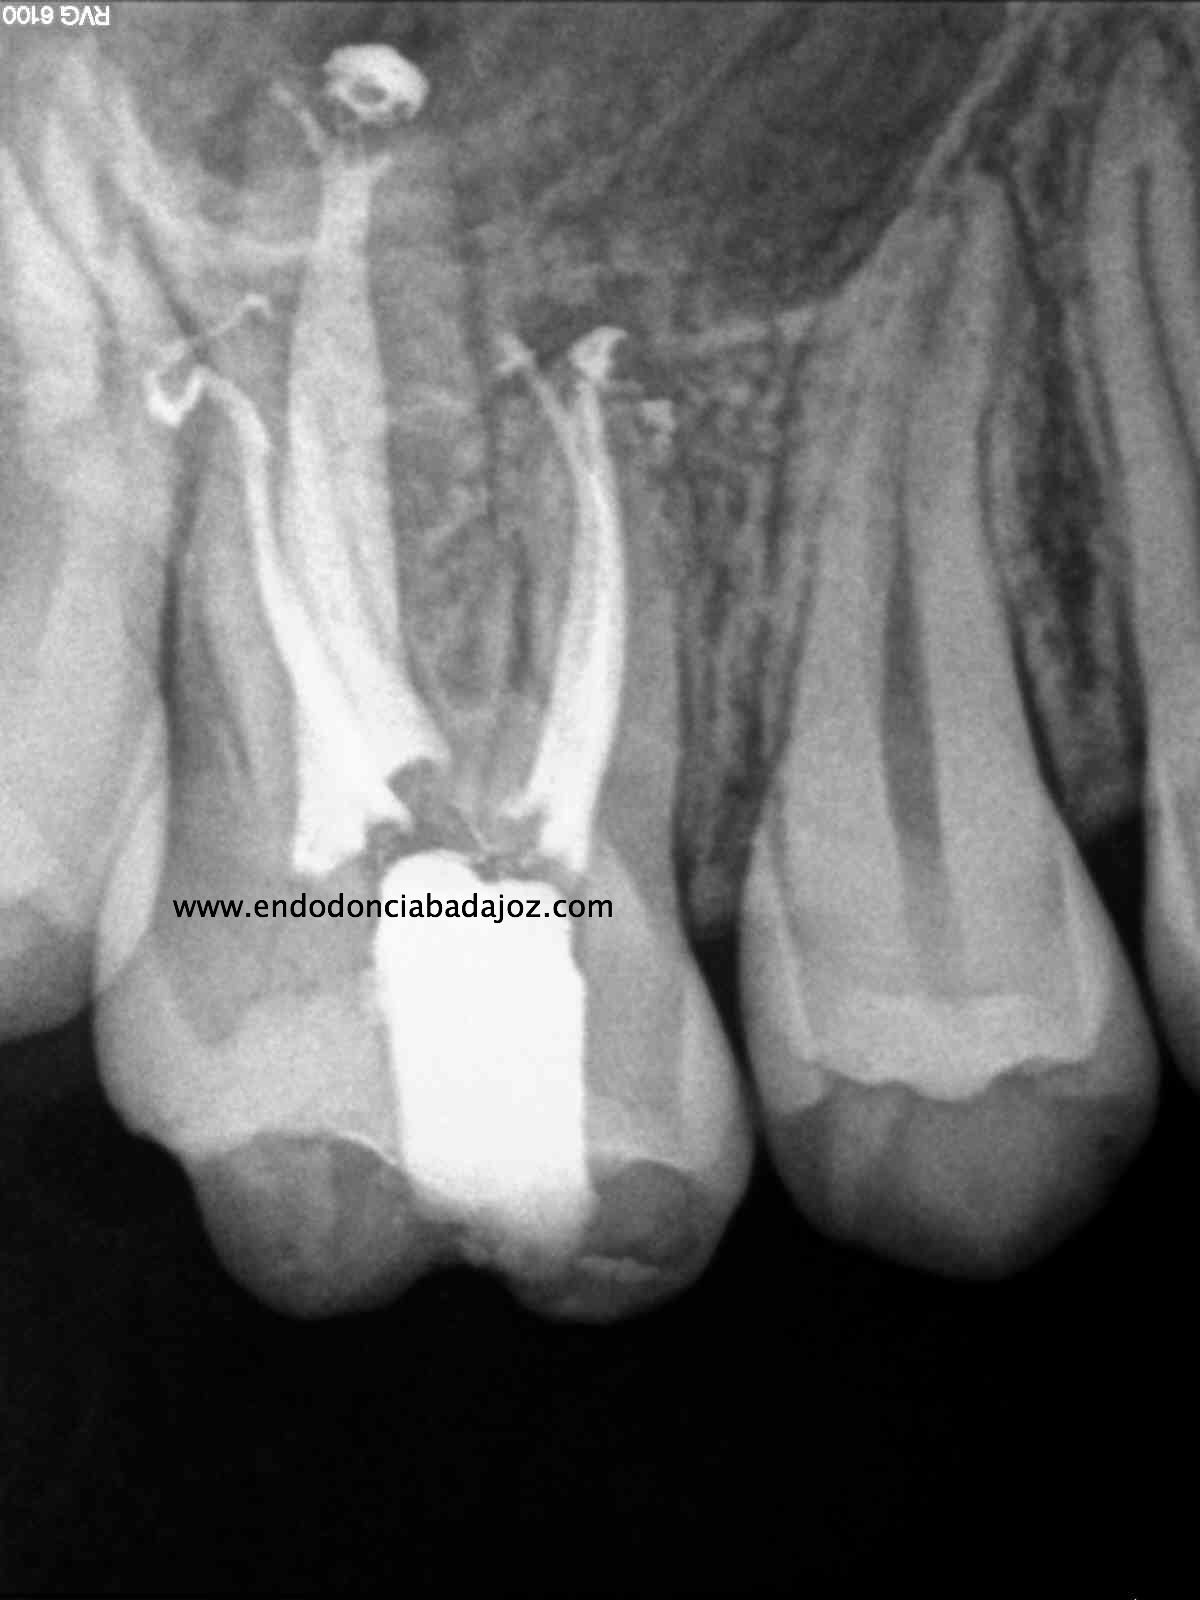

Para cerrar el año, propongo unos casos tres molares superiores:

A) Nos encontramos con un 1.7, con una necrosis pulpar con afectación periapical.

B) Un 1.6 con una pulpitis irreversible.

C) Por último, no encontramos un 1.6 con otra pulpitis irreversible.

Todos los casos los tratamos igual, con ayuda del microscopio, localizamos los cuatro conductos, instrumentamos con sistema Mtwo, y obturamos con sistema de condensación vertical con ola contínua para hacer el downpack y pistola Obtura II para hacer el backfilling.

Lo que tienen estos tres casos en común, y por lo que decido colocarlos, es por la importancia que tiene la irrigación, por que hay veces que aunque en molares superiores localicemos el conducto Mesio-palatino, puede que su salida se bifurque y nuestra lima no pueda seguir el conducto por que tiende a seguir recto uniendose al MV.